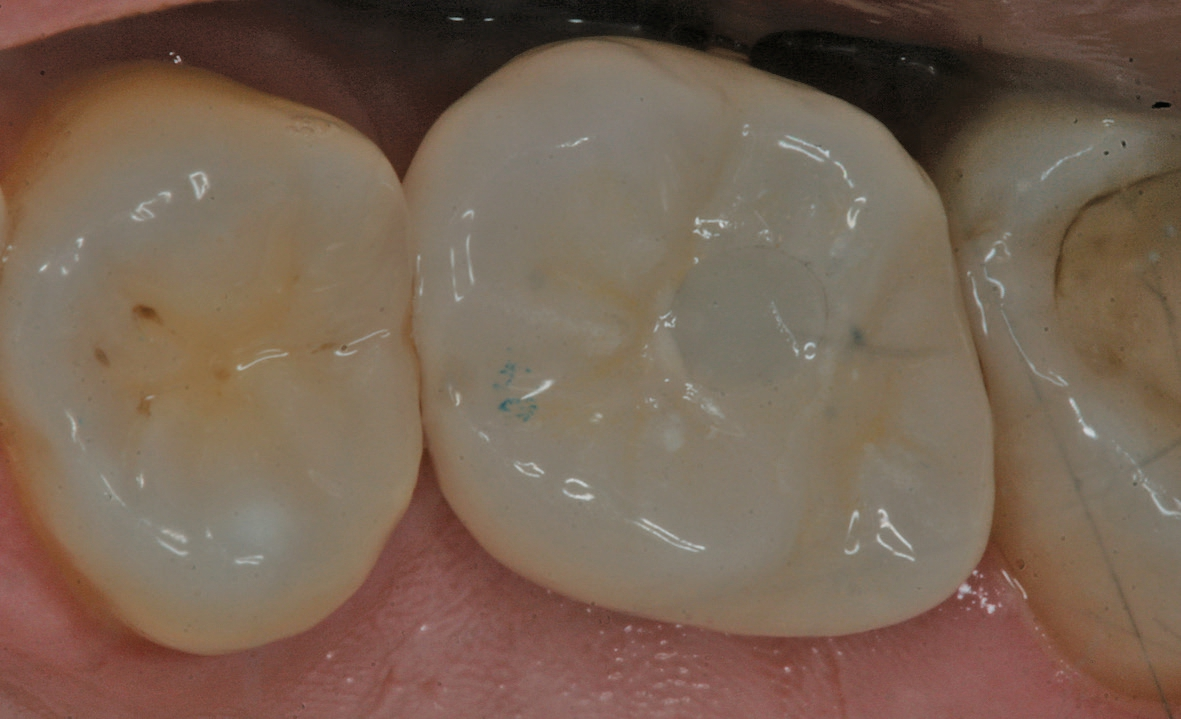

Eine der häufigsten Indikationen für Implantate überhaupt stellt die Einzelzahnlücke nach Verlust eines ersten Molaren dar. Bei den meisten Fällen liegt ein stabiles vertikales Knochenangebot an den Nachbarzähne vor, sodass in der Regel nach Ausheilung des apikalen Granulationsgewebes von einer guten Knochenregeneration auszugehen ist, so dass keine Notwendigkeit der Insertion von kurzen oder ultrakurzen Implantaten gegeben ist. Im Oberkiefer kann bei einer weiten Divergenz der Wurzeln des extrahierten Zahnes es zu einer ausgeprägten Pneumatisation der Kieferhöhle kommen. Daher werden gerade beim jugendlichen Patienten dort dann kurze Implantate eingesetzt, um auf eine Sinusbodenelevation mit einem lateralen Zugang verzichten zu können [3]. Die Implantate können mit oder ohne eine Navigationsschablone gesetzt werden [4]. Da die Lücke begrenzende Nachbarzähne eine gute Orientierung in der mesio-distalen Dimension ermöglichen, kann oftmals auch auf eine Orientierungsschablone verzichtet werden. In der oro-vestibulären Richtung muss der Anwendung des größeren Durchmessers Rechnung getragen werden. Dies kann mit einfachen Positionierungshilfen erfolgen, damit die Implantatachse möglichst zentral in der Kaufläche zu liegen kommt (Abb. 1-8). Die Einzelzahnlücke kann mit einer integrierten verschraubbaren Abutment-Hybrid-Krone oder mit einem Abutment und einer zementierten Krone versorgt werden [5].

Für die Einzelkronen auf ultrakurzen Implantaten können bei achsgerechter Implantatposition daher verschraubbare Abutment- Hybrid-Kronen hergestellt werden. Eine klassische Verblendung mit Keramikmassen auf einen Titanrohling als Abutment zeigt sich jedoch sehr aufwändig und kann zu Veränderungen der Oberfläche im Bereich der Passung der Aufbauverbindung führen. Daher empfiehlt sich die Verwendung einer Klebebasis, die eine genormte Anschlussgeometrie für Keramikrohlinge zeigt oder ein Aufbau, der durch Beschleifen individualisiert zur Aufnahme einer Keramikkrone verwendet werden kann.

Bei der Verwendung einer Klebebasis kann ein mit der Anschlussgeometrie versehener CAD/CAM-Block verwendet werden [9]. Diese stehen als Grünling aus Zirkonoxid- oder Lithium-Disilikat- Glaskeramik (LS2) zur Verfügung, um den Zahnersatz zu fräsen [10]. Nach dem Sintern und dem Einfärben der Zirkonoxidkeramik (ZrO) steht ein korrosionsresistentes, aber in der Regel auch sehr hartes Werkstück zur Verfügung. Daher finden vermehrt LS2-Keramiken Verwendung, die zwar im Vergleich zur Zirkonoxidkeramik eine geringe Biegefestigkeit zeigen, aber für die Anwendung auch für den Seitenzahnbereich freigegeben sind. Klinisch zeigt sich eine geringe Komplikationsrate und vor allem eine hohe Patientenakzeptanz [11]. Neben dem physiologischen Kauverhalten durch die geringere Härte zeichnet sich die LS2-Keramik durch eine bessere Transparenz im Vergleich zu den ZrO-Keramiken aus, so dass besonders im sichtbaren Bereich ästhetisch ansprechende Versorgungen erreicht werden können.